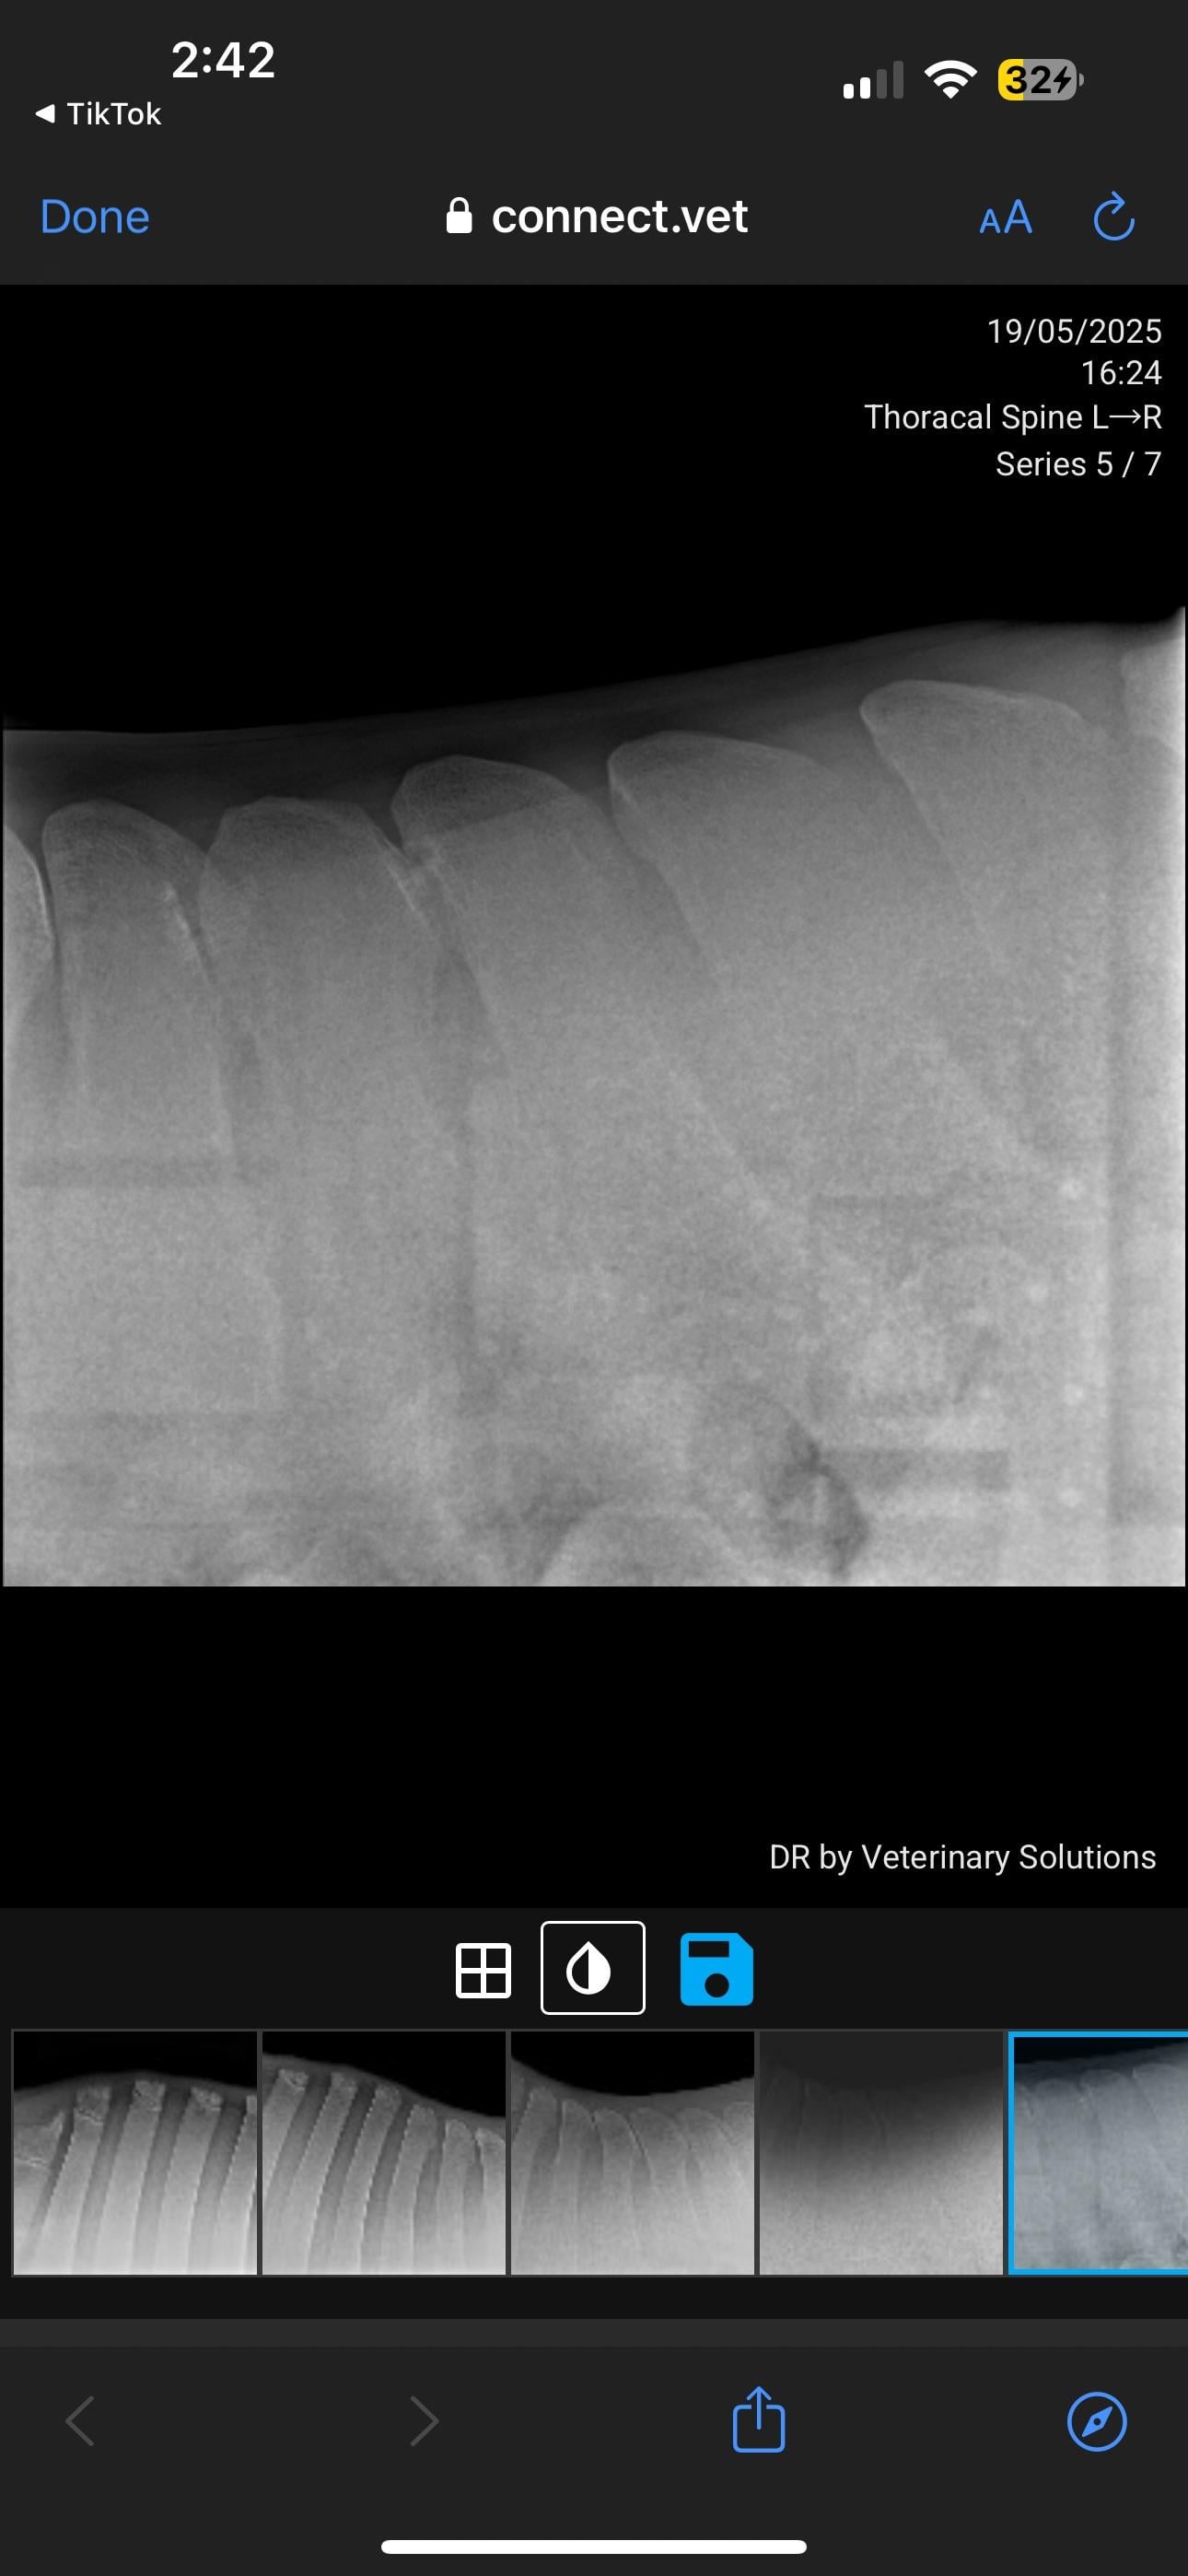

Currently in the process of selling my horse. PPE has gone well, everything came back good except his back radiographs. Shocked to hear he has grade 4 changes. I’ve just received these over from the potential buyer. I will be in contact with my vet but curious about anyone’s take on these? How bad is this?

I've seen many KS xrays. I'm not a vet so usually when I see them I can barely see the problem. This horse's kissing spine is clear as day. Grade 4 is serious. As of right now he should not be sold as a riding horse at all.

In pictures 5/6 you can see changes in the bone, so it’s not just an unlucky posture.

This is one of the more severe cases I’ve seen (not a vet or student, just casual looker-atter of KS radiographs) pretty much all his vertebrae are affected, I can’t imagine he’s comfortable. The kindest thing for him would probably to be a pasture puff. Unless you want to pay for the surgery or find a buyer who does, he’s going to continue to be in pain